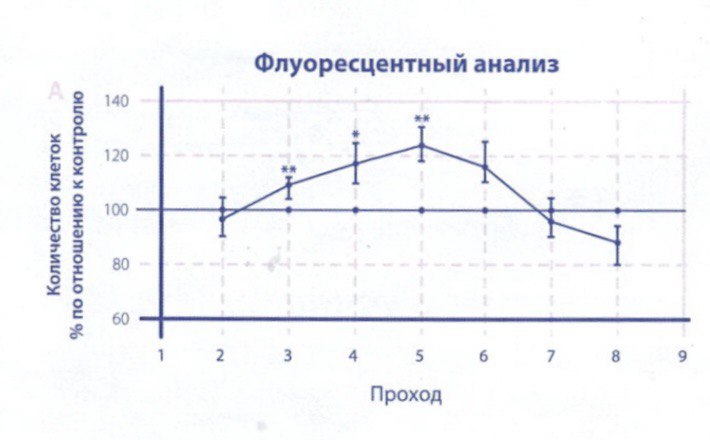

В результате стимуляции радиочастотными волнами начинается процесс регенерации тканей. Это может включать в себя увеличение производства коллагена и эластина, укрепление мышц и связок, а также уменьшение воспаления и отечности.

Нагревание тканей при помощи радиочастотных волн стимулирует биологические процессы в организме. Оно активизирует метаболизм, улучшает микроциркуляцию крови и лимфодренаж, а также стимулирует клетки к более активной работе.